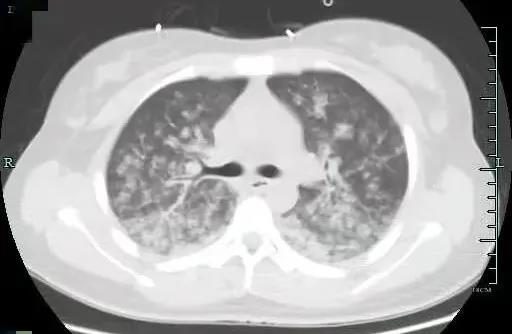

两种原因造成的结果相似,但治疗方案截然不同。根据小月的肺动脉CTA、肺部CT等检查结果显示,小月为肺脂肪栓塞,此时小月的肺部已是白茫茫一片,就像暴风雪一样,脂肪进入她肺部,刺激血管发生痉挛,产生严重的炎症因子风暴!